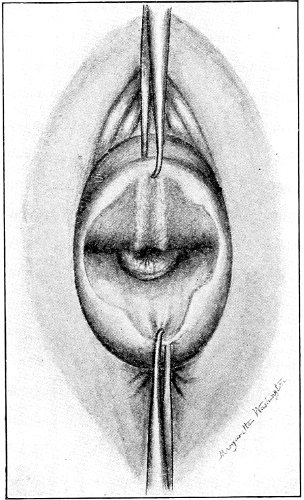

Slight Median laceration of the Perineum.—In this injury the tear takes place through the fourchette. Posteriorly it may extend as far as the sphincter ani muscle. Upward it may extend for an inch up the posterior vaginal wall. The appearance of this tear is shown in Fig. 33. It will be noted that, as this tear takes place in the median line, none of the muscles that support the perineum are involved, nor are the planes of fascia injured. The perineum is slightly split, and the insertions and origins of the muscles and the fascia are slightly separated. The supporting structures of the perineum and the pelvic floor are, however, uninjured.

Fig. 33.—Recent slight median laceration of the perineum: sutures introduced.

If this tear is detected after labor, it should be closed by the immediate operation. A slight tear involving chiefly the cutaneous aspect of the perineum should be closed by three or four sutures introduced from the outside, as in Fig. 33. The needle should be introduced about a quarter of an inch from the edge of the wound. It should not be passed parallel with the plane of the lacerated surface, but should be swept outward and then inward toward the 68 angle at the bottom of the tear (Fig. 34). It may either emerge at the angle and be re-introduced, or it may be passed directly through to the skin-margin on the opposite side of the wound. If the suture is passed in this way, there will be perfect apposition throughout the whole surface of laceration. If the sutures are improperly passed, there may result only apposition of the skin-edges.

Fig. 34.—Diagram representing the correct and the incorrect method of passing the suture for closure of slight perineal laceration.

If the laceration extends up the posterior vaginal wall, two sets of sutures must be introduced—one on the vaginal aspect of the tear, and one on the skin aspect (Fig. 35).